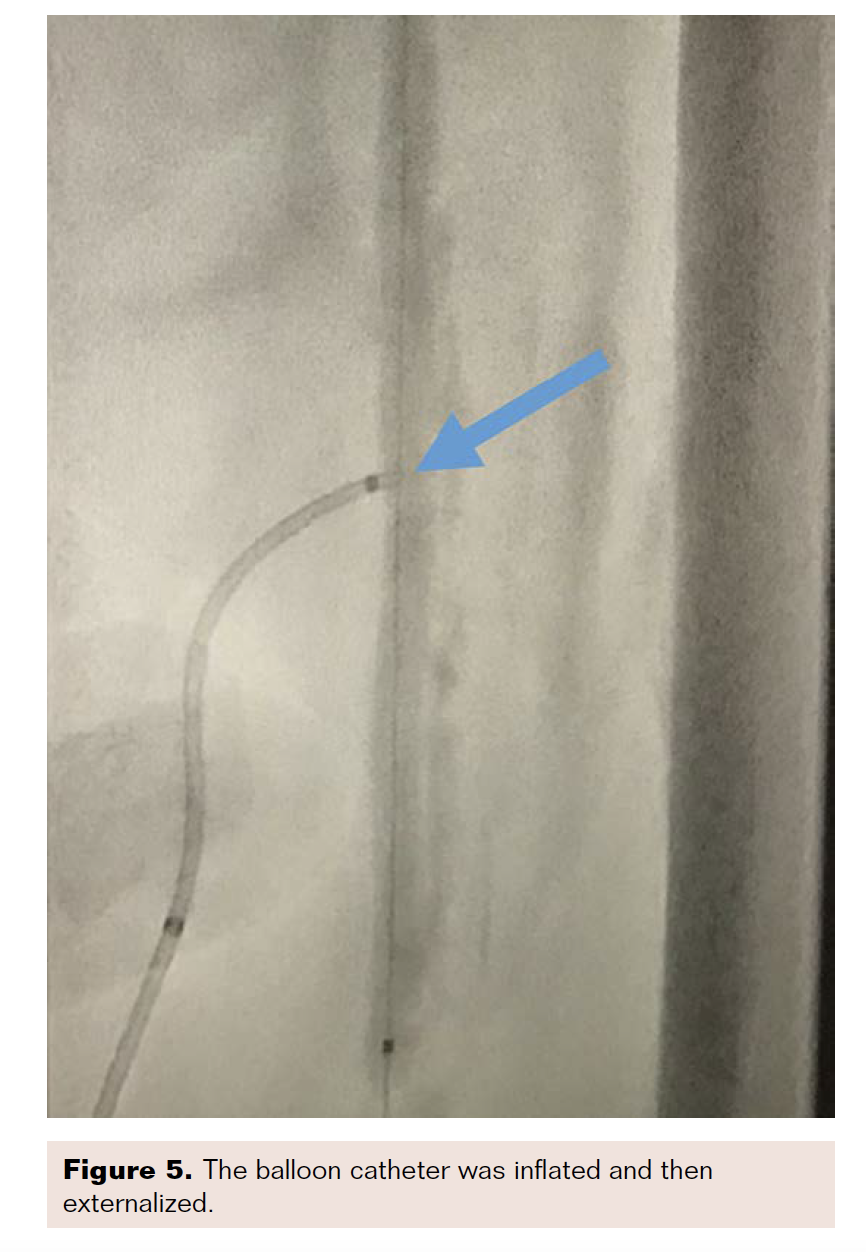

Internal tamponade of the left SFA access site was performed using a 4 × 150 cm Advance PTA balloon (Cook Medical) for 180 seconds, while removing the direct SFA access and Astato wire (Figure 5). We then turned our attention to the mid-SFA occlusion. An 18 g Victory wire (Boston Scientific) was used to cross the lesion, followed by a 3 × 40 mm, .014-inch LP balloon (Cook Medical), followed by a 5 × 200 mm Armada balloon (Abbott) to dilate the lesion (Figure 6). A dissection occurred in the SFA and popliteal arteries (Figure 7), so we placed a 6 × 250 mm Viabahn covered stent (Gore Medical) from the ostium to the distal SFA, and a